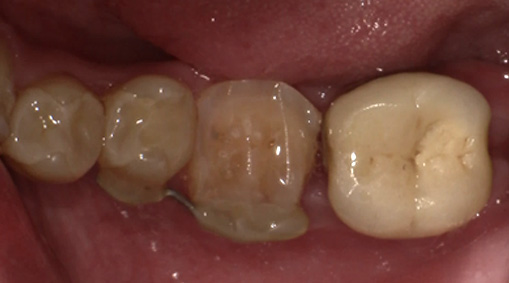

術前・術後の比較

| 術前 | 術後 |

|---|---|

![]() |

9日目 最終的な被せ物をいれます。